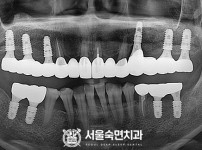

임플란트-전후사진4